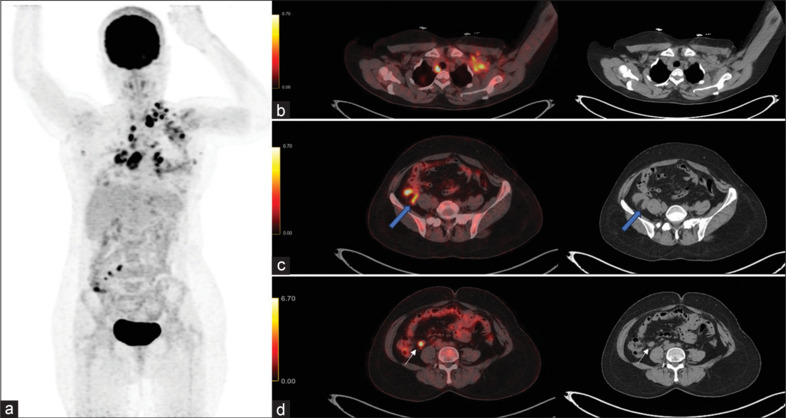

The interpretation of F-18 fluorodeoxyglucose positron emission tomography/computed tomography (FDG-PET/CT) scans can be confounded by incidental findings, as illustrated in this case of a 47-year-old woman with a history of breast carcinoma. Following neoadjuvant chemotherapy and mastectomy, she underwent FDG PET/CT for disease evaluation, revealing unexpected hypermetabolic activity in the right iliac fossa corresponding to acute appendicitis. Thus, FDG PET/CT has the potential to uncover treatable conditions beyond cancer and imaging findings need clinical correlation.

对F-18氟脱氧葡萄糖正电子发射断层扫描/计算机断层扫描(FDG-PET/CT)的解释可能会因偶然发现而混淆,正如本病例中一位47岁的乳腺癌病史女性所示。在新辅助化疗和乳房切除术后,她接受了FDG PET/CT进行疾病评估,发现右侧髂窝意外出现急性阑尾炎的高代谢活动。因此,FDG PET/CT有潜力发现癌症以外的可治疗疾病,影像学结果需要临床相关性。